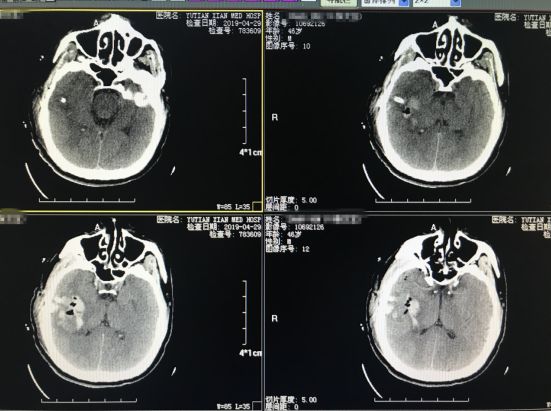

入院后紧急行 “小骨窗开颅血肿清除术”,时间就是生命,经过紧张的术前准备,手术顺利实施,成功为该患者清除了颅内血肿,血肿清除后脑压不高,还纳骨瓣并固定,术后第2天患者神志清醒,问话能答,左侧肢体活动较前明显好转。

▉术后第二天复查颅脑CT如图所示